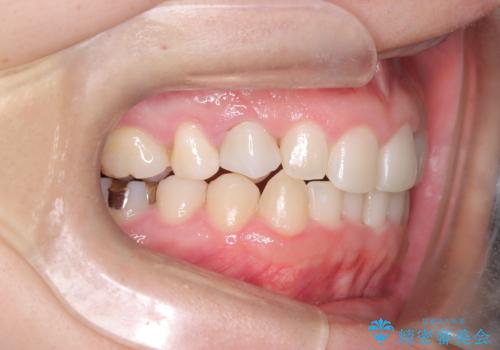

前歯のガタつきと逆の噛み合わせを、短期間のインビザラインで改善

- 前歯の叢生(ガタつき)と、上下の噛み合わせが一部逆になっている反対咬合を主訴にご来院されました。精密検査の結果、前歯の移動だけでは不十分で、歯列全体のアーチを整えながらスペースを確保する必要があると診断。

中等度の症例に最適で最大26ステージ(※プランによる)のマウスピースが使用可能な**「インビザライン・モデレート」**を選択しました。これにより、抜歯をせずに歯列を横に広げ(側方拡大)、前歯を並べる十分なスペースを作りながら反対咬合を確実に改善する計画を立案しました。

反対咬合の解消: 内側に入っていた前歯を、マウスピースの力を利用して外側へ押し出しました。同時に、下顎の歯並びも微調整することで、スムーズに正常な噛み合わせへと誘導しました。